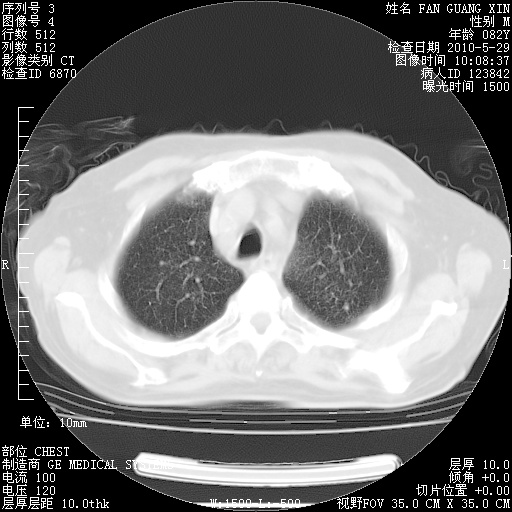

还需要哪些辅助检查?我们医院排除真菌感染没有任何检验方法,胸片好像能够排除肺部真菌感染。

补充:ENA化验全部阴性。免疫五项(IgG、IgA、IgM、C3、C4)只有C4略高。

CD3+ T细胞/淋巴细胞 46% (参考值50.00~84.00%)

CD3+CD4+ T细胞/淋巴细胞 21% (参考值27.00~51.00%)

CD3+CD8+ T细胞/淋巴细胞 25% (参考值15.00~44.00%)

CD3+CD4+ T细胞/CD3+CD8+ T细胞 0.84 (参考值0.71~2.78)

T细胞亚群是治疗5天采血。